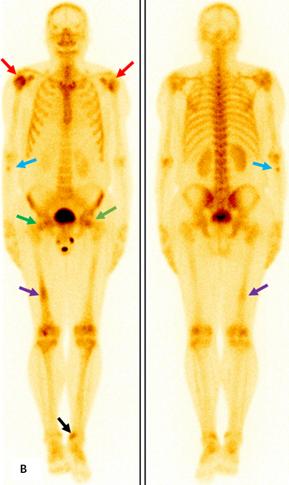

前列腺MRI示:前列腺移行帶結節狀異常信號,建議穿刺活檢;前列腺增生,PI-RADS2;雙側股骨頭信號異常,不排除轉移瘤(圖A)。為評估骨轉移情況遂行ECT全身骨顯像檢查,示:雙側肱骨頭、雙側股骨頭、右側前臂上段、右側股骨中下段代謝異常增強(圖B)。骨顯像不符合前列腺癌骨轉移典型表現,同時結合患者胸部CT(圖C)平掃示右側腋窩多發淋巴結腫大,生化檢查示乳酸脫氫酶620U/L(97-270),懷疑系血液系統腫瘤,建議患者行PET/CT檢查。PET/CT示:右側腦室內高密度灶,多發FDG代謝增高淋巴結及多發骨骼/骨髓FDG代謝增高灶,考慮淋巴瘤(圖D)。

ECT全身骨顯像示雙側肱骨頭(紅箭)、雙側股骨頭(綠箭)、右側前臂上段(藍箭)、右側股骨中下段(紫箭)、左側脛骨下端(黑箭)代謝異常增強。